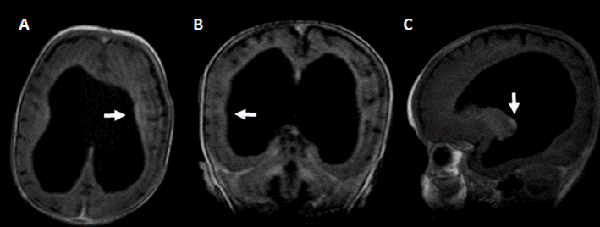

Actualmente tras 14 meses de seguimiento, la paciente se encuentra asintomática y en el control de resonancia magnética realizada a los 12 meses de post quirúrgico donde se observó disminución del tamaño ventricular ausencia de tabiques interventriculares, y ausencia de realce tras la administración de contraste (Figura 2).

Figura 1: RM de encéfalo prequirúrgica: A) corte axial, B) coronal y C) sagital, ponderado en T1 con contraste. Se observa dilatación del sistema ventricular, ausencia de septum pellucidum, adelgazamiento de sustancia blanca periventricular y cuerpo calloso, con realce ependimario compatible con ventriculitis (flecha).

Figura 2: RM de encéfalo realizada a los 12 meses post quirúrgico de la colocación de la DVP: A) corte axial, B) coronal, C) sagital, ponderado en T1 con contraste. Se observa disminución del tamaño ventricular en comparación con resonancia previa, sin realce ependimario tras la administración de contraste.